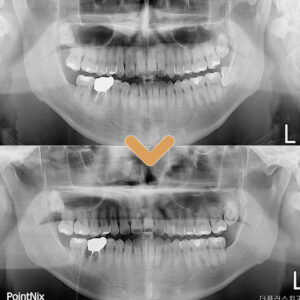

20. 수암동치과 양쪽 어금니 모두 빠진지 오래되어 식사가 불편해요.

수암동치과 양쪽 어금니 모두 빠진지 오래되어 식사가 불편해요.   안녕하세요. 모든 진료에 진심을 다하는 곳, 더플러스치과입니다. ​ 현대 평균 연령이 높아지면서 초고령화 시대가 되고 있는데요.   나이를 먹으면서 신체도 자연스럽게 노화되기 마련입니다.   치아 역시 노화로 인한 잇몸의 약화가 생겨 더보기…